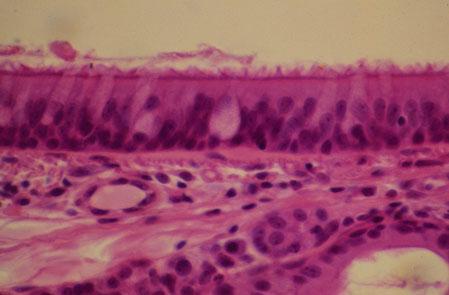

II-45 (5) Slide 73, Trachea (H&E). Examine aspects of the respiratory epithelium: cilia, basal body (dark line at cell apex), goblet cells, pseudostratified columnar cells and basement membrane.